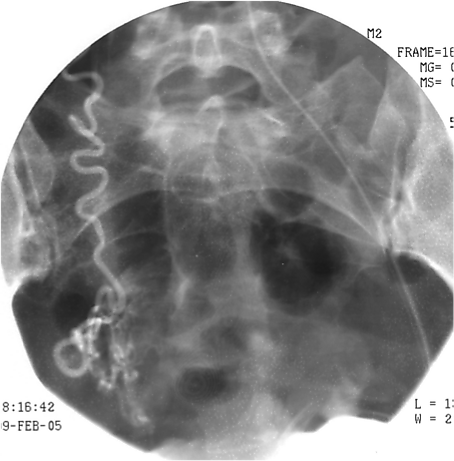

Эмболизация маточных артерий (ЭМА) — способ лечения миомы матки без хирургической операции. Эффект достигается за счет перекрытия кровотока в узлах миомы с помощью специального препарата, который вводится в артерии матки по тонкой трубке (катетеру) через бедро. Препарат содержит мелкие шарики (эмболы), которые перекрывают артерии миомы, после чего она погибает в течение нескольких часов. Эмболизация маточных артерий позволяет во многих случаях отказаться от необходимости удаления матки при миоме и сохранить репродуктивную функцию.

При миоме ЭМА вызывает прекращение кровотока по ветвям маточных артерий, кровоснабжающим миому. Разный диаметр питающих миому ветвей и ветвей, питающих миометрий, приводит к минимальному воздействию на сосуды неизмененного миометрия. После прекращения кровоснабжения мышечные клетки, формирующие миому, гибнут. В течение нескольких недель происходит их замещение соединительной тканью. Затем в процессе «рассасывания» этой ткани происходит значительное уменьшение и/или полное исчезновение узлов, а симптомы миомы проходят.